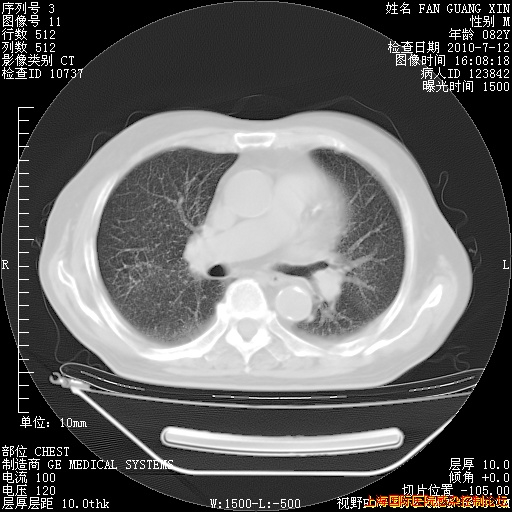

补发6月12日肺部CT肺窗

6月12日肺窗